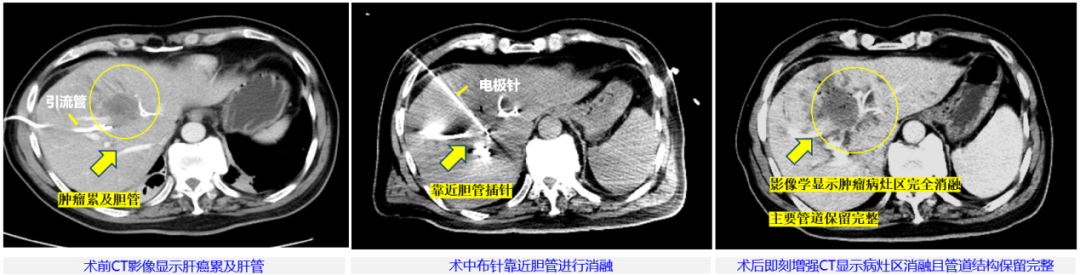

本次治疗病例为57岁男性,临床诊断肝内胆管细胞癌局部转移,侵犯肝门伴梗阻性黄疸,主病灶45mm×36mm,已行双侧PTBD(经皮经肝胆管穿刺引流术)减黄处理。由于病灶位于肝门部,紧邻左侧门静脉及胆囊,这里密布肝动脉、门静脉和胆管等重要脉管结构,无法进行手术切除根治,也不适合各种冷/热消融治疗。董家鸿牵头肝胆胰中心多学科讨论后决定,为患者进行具有脉管?;び攀频摹拔⒛傻丁毕谥瘟?。

整个手术过程中,患者行局部麻醉,在B超联合CT引导下使用“微纳刀”通过单针对病灶区进行消融,消融过程历时15分钟。术中未使用任何肌松剂,也没有采用气管麻醉,患者始终处于清醒状态,可与医生交流。脉冲施加过程中未见肌肉有明显收缩反应,患者也无明显的疼痛的感觉,术后即刻增强CT复查发现,肿瘤病灶区在影像学上已显示全部消融,邻近胆管、血管未见损伤。随后患者安全返回病房,术中术后生命体征平稳、未发现不良反应。